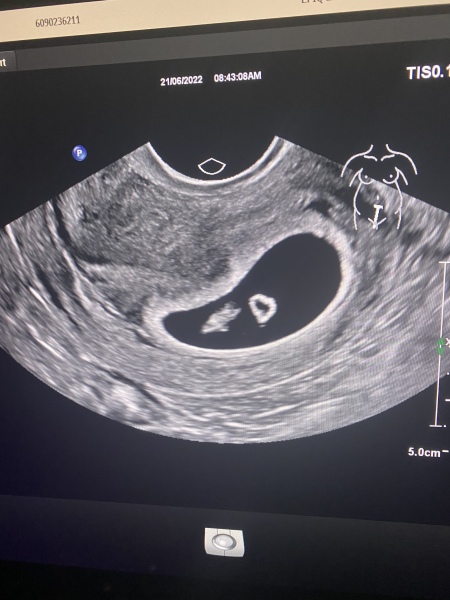

This was my scan at around 6 weeks so you may be able to see something. I would take the scan option